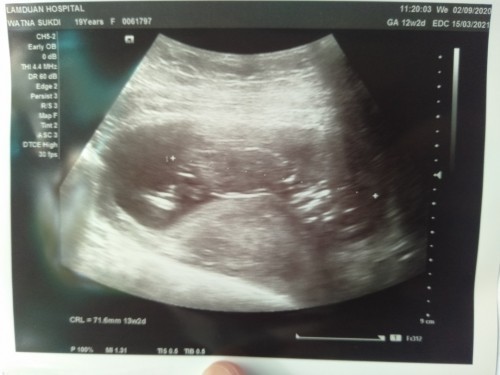

12Wจ้า